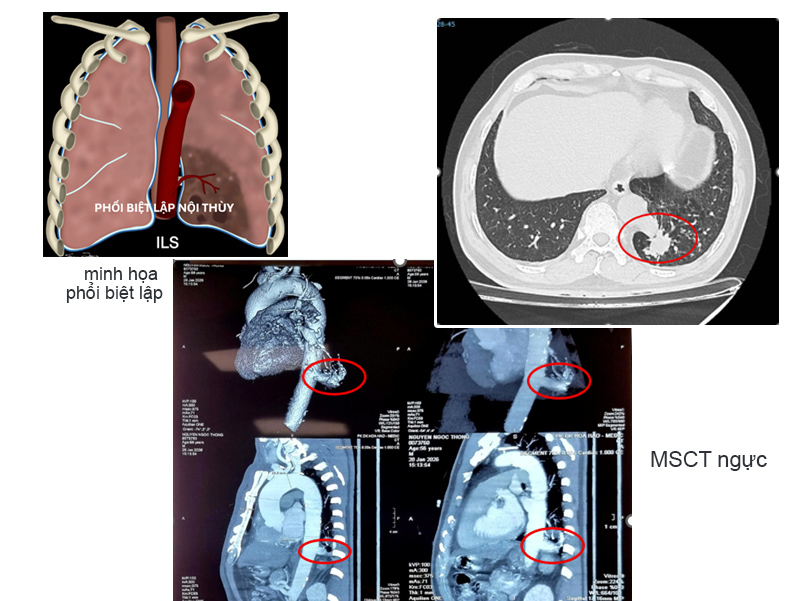

Bệnh nhân N.N.T. (56 tuổi, Tây Ninh) tình cờ phát hiện tổn thương ở thùy dưới phổi trái khi khám sức khỏe định kỳ. Kết quả chẩn đoán xác định ông mắc phổi biệt lập nội thùy, khối kích thước 23 x 26 mm. Đáng chú ý, động mạch nuôi khối này xuất phát trực tiếp từ động mạch chủ ngực xuống, đường kính lên tới 17 mm - kích thước lớn, tiềm ẩn nguy cơ chảy máu nghiêm trọng nếu không xử lý kịp thời.

Phổi biệt lập (Bronchopulmonary Sequestration - BPS) là dị tật bẩm sinh hiếm, chiếm khoảng 0,15-6,4% các dị tật phổi. Bệnh gồm hai dạng: nội thùy (khoảng 75%) và ngoại thùy (25%), thường gặp ở thùy dưới phổi trái.

Đây là phần mô phổi phát triển bất thường từ thời kỳ phôi thai, không có chức năng hô hấp và không thông với đường dẫn khí bình thường. Nguy hiểm nhất là nguồn máu nuôi của khối này không đến từ động mạch phổi mà từ động mạch hệ thống, thường là động mạch chủ ngực hoặc bụng.